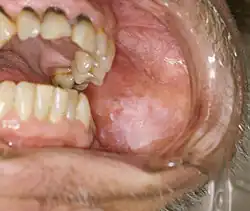

Classic Wickham's striae of non-erosive lichen planus in the left buccal mucosa (left cheek)

Oral lichen planus (also termed oral mucosal lichen planus), is a form of mucosal lichen planus, where lichen planus involves the oral mucosa, the lining of the mouth.[39] This may occur in combination with other variants of lichen planus. Six clinical forms of oral lichen planus (OLP) are recognized:[40]

Reticular

The most common presentation of oral lichen planus (OLP) is characterised by the net-like or spider web-like appearance of lacy white lines, known as Wickham's striae.[41] This is usually asymptomatic. Reticular OLP may progress to the more severe subtypes, such as the erosive form, if left untreated.[2]